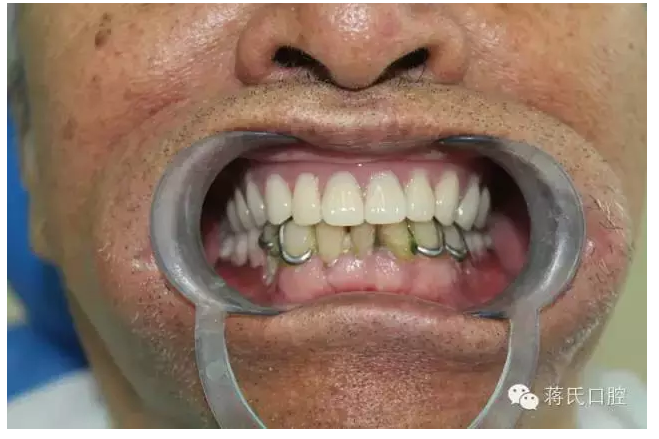

主訴 要求修復(fù)缺失牙,因為自身異物感重,已于外院修復(fù)幾次義齒,均不能使用,要求花費最少的錢解決吃飯問題。

患者情況 男 76歲 ,三類骨。腭咽反應(yīng)重。治療方案 1盡量減少種植費用。

4活動義齒雙重冠修復(fù)

5去除上頜基托

6時間 4個月